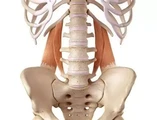

| Par images | Réponse | % Correct |

|---|---|---|

| diaphragme | 84%

|

| psoas | 66%

|

| carré des lombes | 57%

|

| iliaque | 55%

|